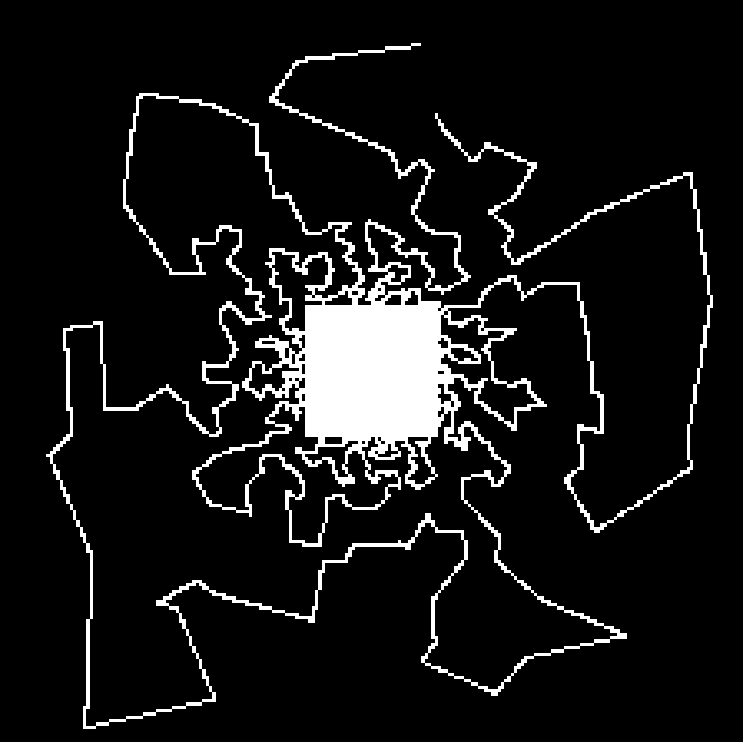

Compressed Sensing (CS) provides a theoretical framework to justify the downsampling of -space (2D or 3D Fourier domain) in Magnetic Resonance Imaging (MRI). CS-MRI is usually based on independent random drawing of -space locations according to a prescribed density. From recent theoretical works [3, 4], one can derive an optimal sampling density that reduces at most the number of samples collected in MRI without degrading the image quality at the reconstruction step [5, 6]. In [7], simulations show that distributions with radial decay (see Fig. 1(a)) with full -space center acquisition perform better in numerical experiments.

However, such sampling schemes are not performed along continuous lines and thus not physically plausible in MRI because of the constraints involved on the magnetic field gradient (magnitude and slew-rate). In [8], we have proposed a new approach to design continuous sampling trajectories based on the solution of Travelling Salesman Problem (TSP), as illustrated in Fig. 1(b). The specificity of this approach is that the empirical distribution of the trajectory can approximate any prescribed distribution . Such a curve is called a -Variable Density Sampler (-VDS). Unfortunately, continuity of the sampling trajectory is not a sufficient condition in MRI and it is not clear how to design admissible gradient waveforms to traverse such a trajectory.